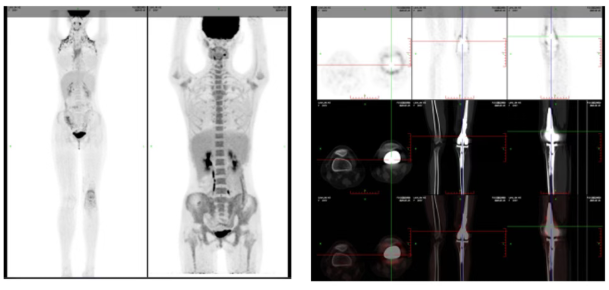

*PET-CT 影像检查图